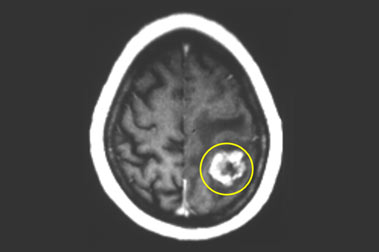

בדוגמה שבתמונות, רדיוכירורגיה הופעלה כדי לטפל בגרורה בעלת נפח די גדול בסמיכות לקליפה המוטורית של המוח (האזור ששולט על התנועות בגפיים בפלג הגוף הנגדי).

ללא צורך באשפוז, הרדמה או חתך ובשהיה של שעות ספורות בבית החולים. ההקרנה המדויקת והחדה חיסלה לחלוטין את הגוש הגרורתי שנעלם בהדרגה.

בזמן הרדיוכירורגיה

כעבור חודשיים